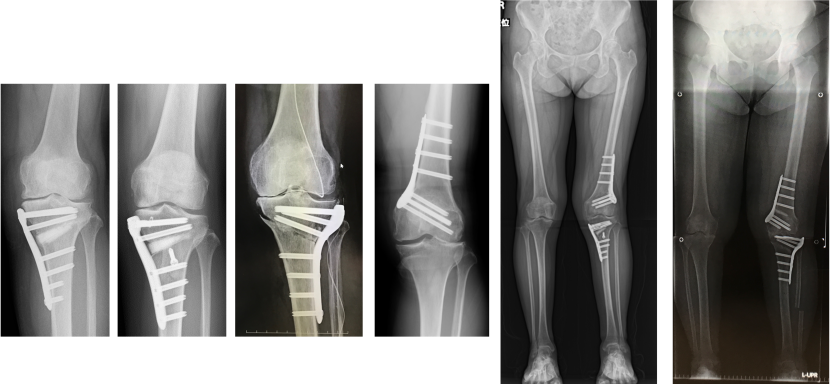

高位脛骨骨切り術

日本人の多くはO脚変形を伴っており、内側型の変形性ひざ関節症に罹患しやすいと言われております。下腿(脛骨)を矯正し、内側にある荷重軸を外側に移動することで損傷した軟骨や半月板への負荷を減じることを目的とします。我々は、同時に関節内治療といわれる半月修復術(制動術・縫合術)も併用することで、可能な限り関節を温存し、膝機能の回復を目指しております。下腿(脛骨)の矯正だけでは不十分な際には 大腿骨の矯正も行います。骨切り術には複数の術式があり、その患者さんの膝の状態に併せて術式を選択しております。

またX脚を伴う外側型の変形性ひざ関節症に対しては、大腿骨遠位骨切り術にて治療しております。